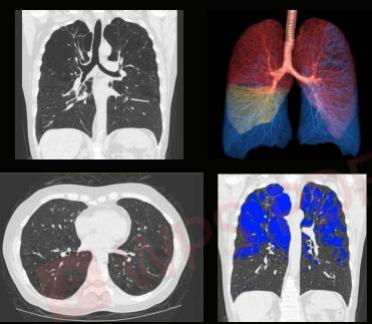

不到1s内完成0.6mm的胸部检查

APEX CT在心脏检查方面,完全革新了以往的复杂检查流程:不需要控制心率,不受心律变化影响,甚至不需要控制呼吸。患者完全在自然状态下接受检查,只需在一个心跳内就完成了整个心脏 CT扫描,这对疑难冠脉病变、血管变异、先天性心脏病等疾病的治疗,都有着重要的意义。

不仅如此,APEX CT对微小病灶的检出能力也显现出无与伦比的优势。传统 CT 扫描心脏冠脉,只能看到一级二级的血管,而 APEX CT可以看到三级、四级,甚至更小的分支;传统CT对直径1毫米以下的血管很难拍出清晰图像,而 APEX CT却可以做到,这意味着能看到更多的微小病灶。